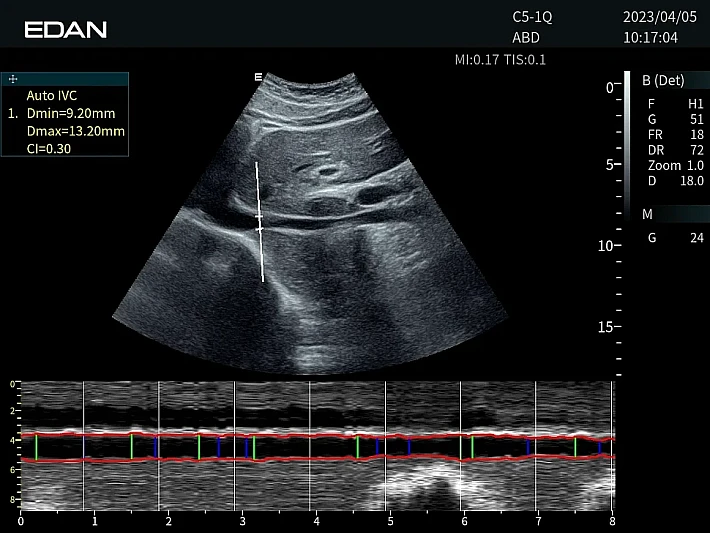

Медицинское оборудование и сервисное обслуживание